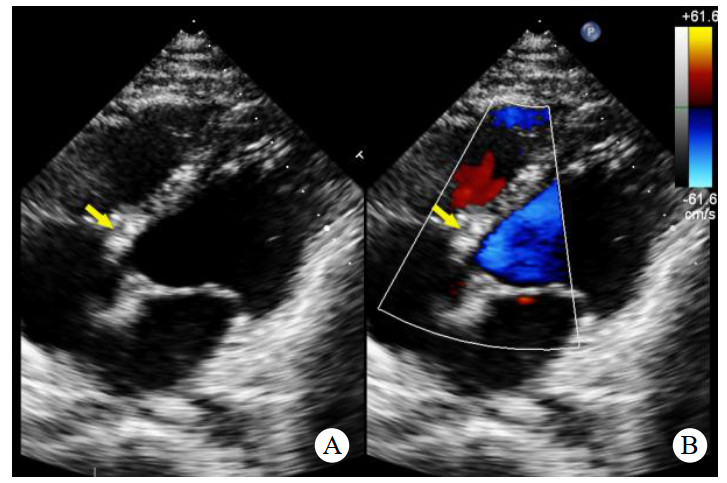

辅助检查如下。实验室检查:高敏C反应蛋白(hs-CRP)和红细胞沉降率(erythrocyte sedimentation rate, ESR)轻度升高。心电图:正常窦性心律,无ST段异常改变。胸部CT:双侧肺门中心对称分布的斑片状高密度影,部分实变,伴空气支气管征,病变边缘模糊。超声心动图:二维超声(2D)主动脉短轴切面显示右乏氏窦瘤破裂(ruptured of ASV, RASV),破入右心房形成“囊袋状”结构,长约1.7 cm,基底部破口内径约0.8 cm(图 1A)。彩色多普勒(color Doppler flow imaging, CDFI)显示全心动周期的左向右分流(图 1B)。连续多普勒(continuous doppler, CW)测得连续分流。室间隔内见4.0 cm×0.7 cm无回声区(图 2A),CDFI显示彩色血流信号随心动周期进出该无回声区(图 2B),考虑室间隔夹层瘤(dissecting aneurysm of the interventricular septum, DAIS)。实时双平面成像同步显示窦瘤破口与室间隔夹层相延续。应用Philips TrueVue三维(three-dimensional, 3D)超声心动图成像模式直观展示室间隔夹层瘤的立体结构(图 3)。

| 注:A为2D超声显示室间隔内无回声区(黄色箭头);B为CDFI显示彩色血流信号进出室间隔无回声区 图 2 2D及CDFI显示左室短轴二尖瓣水平切面室间隔夹层动脉瘤 |